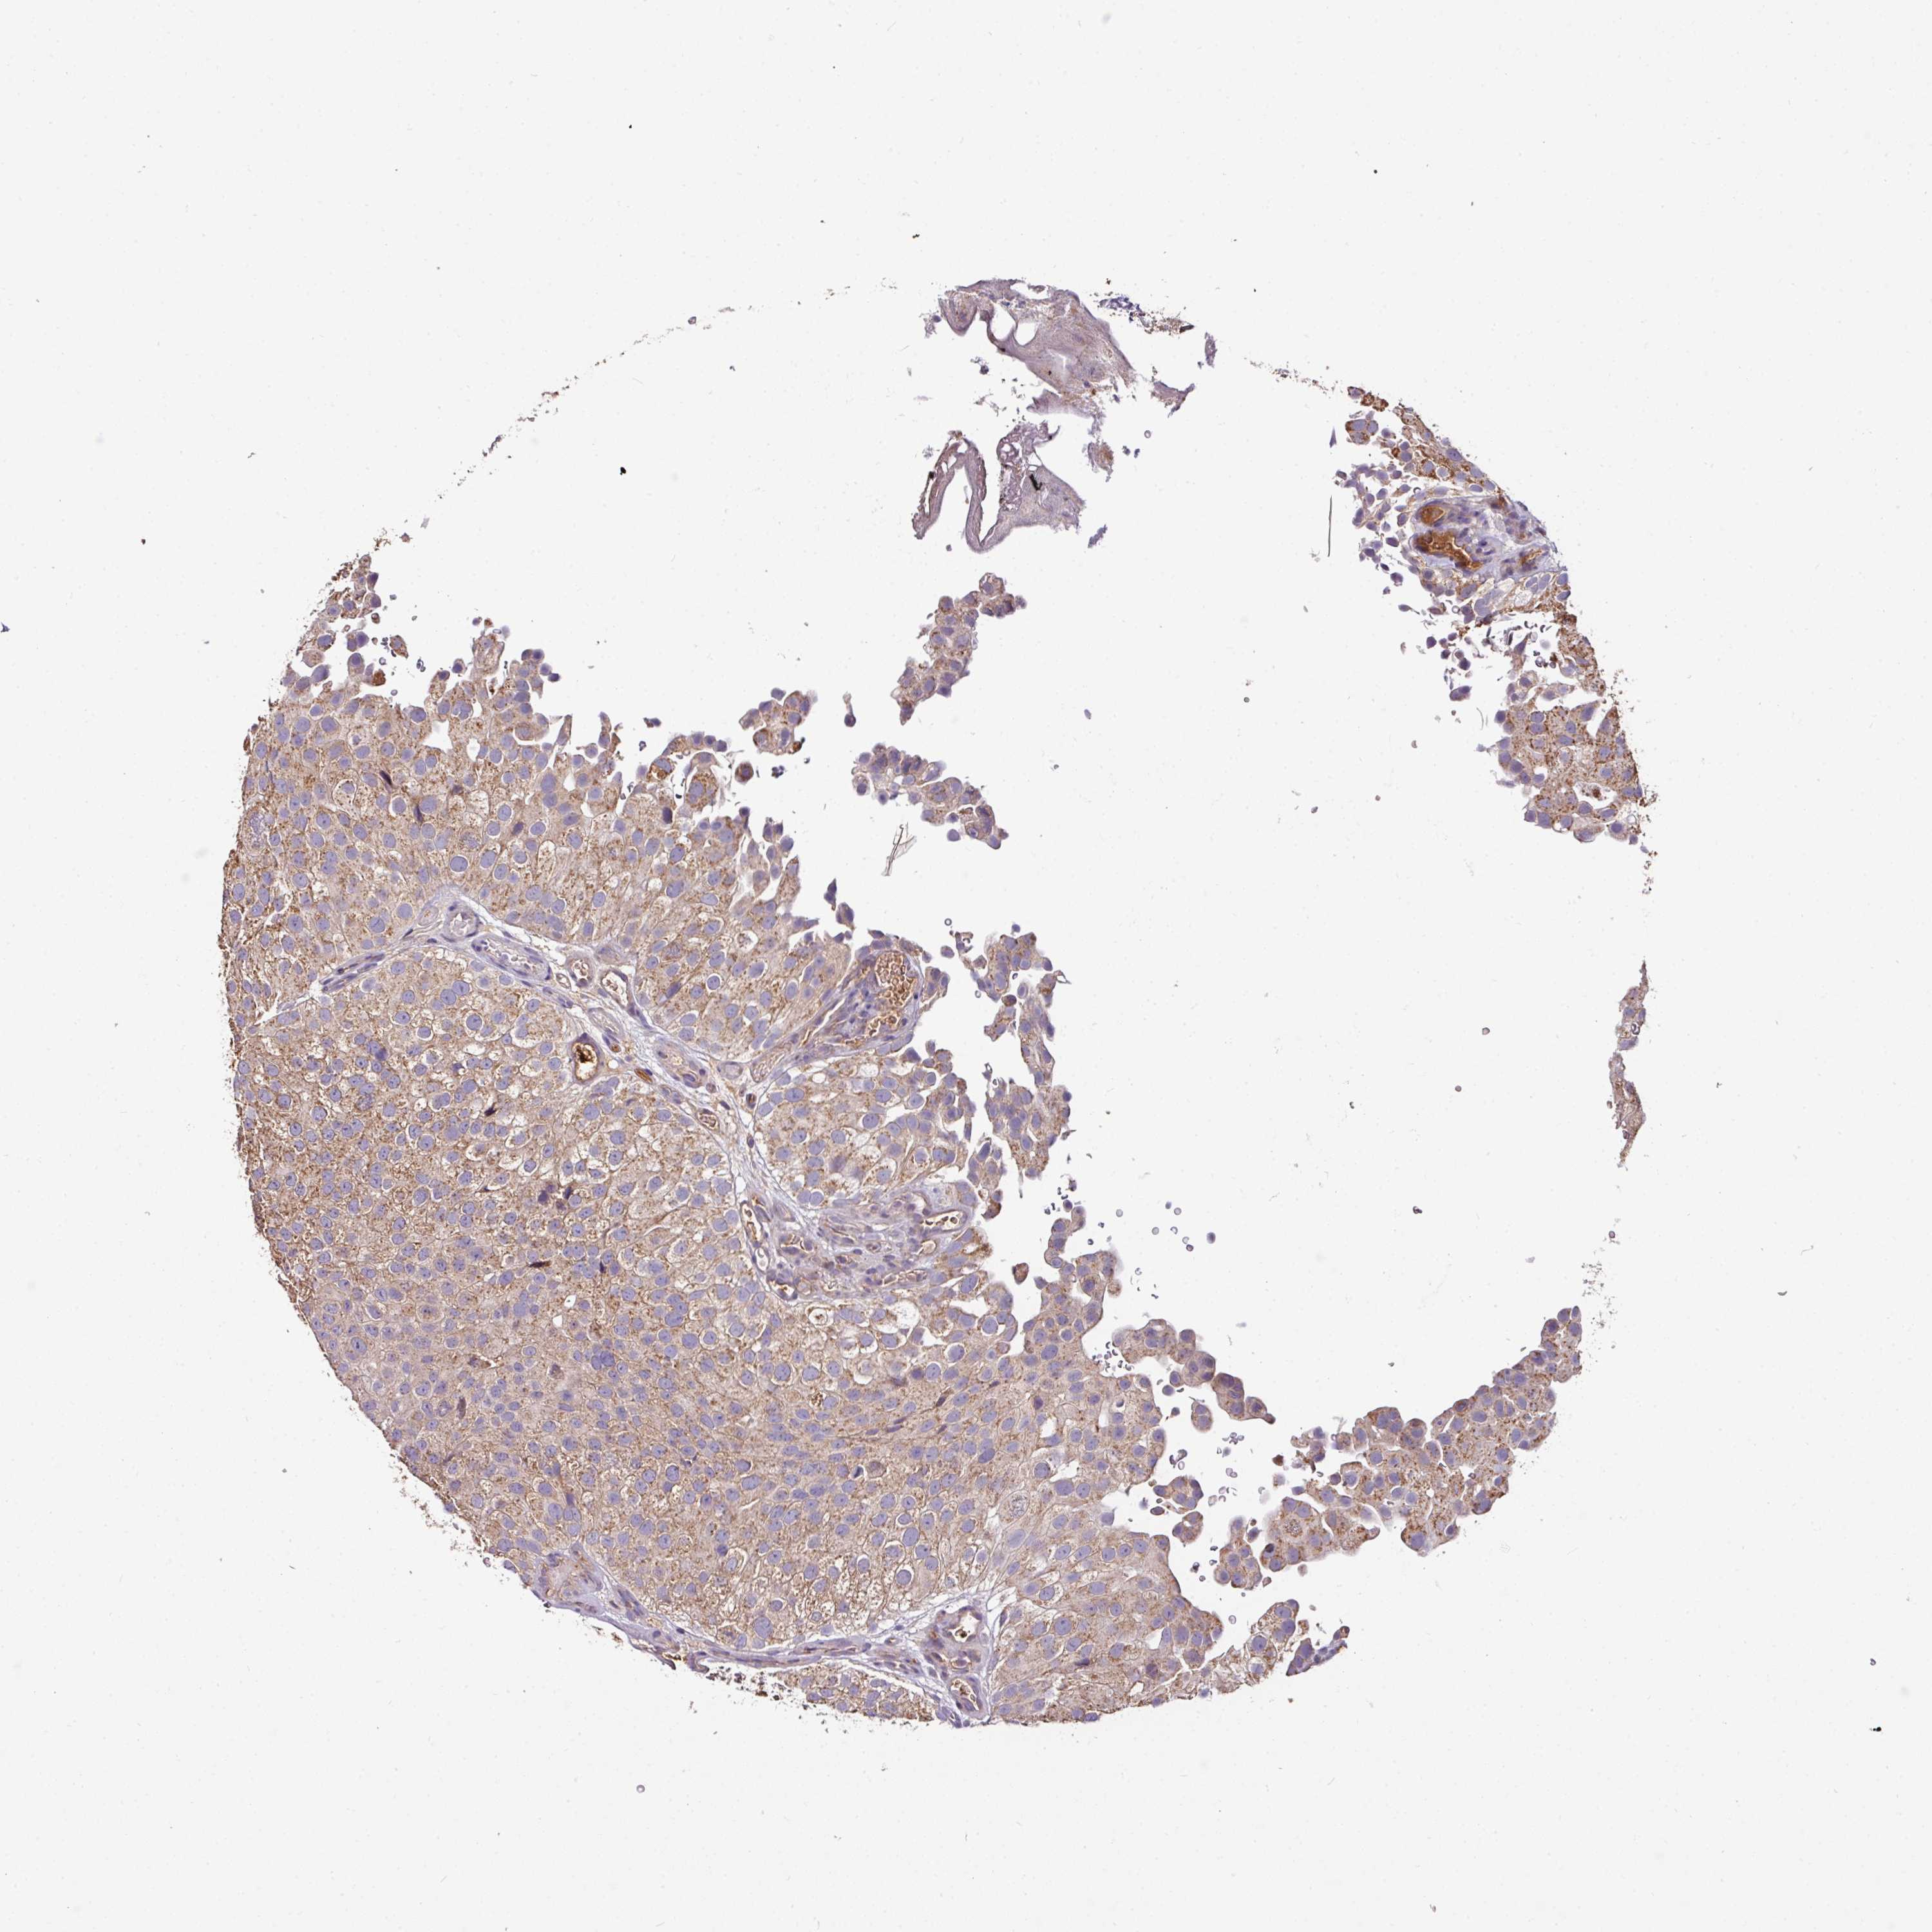

UROTHELIAL CANCER - Protein expressioni

A mouse-over function shows sample information and annotation data. Click on an image to view it in a full screen mode. Samples can be filtered based on level of antibody staining by selecting one or several of the following categories: high, medium, low and not detected. The assay and annotation is described here.

Antibody stainingi

Antibody staining in the annotated cell types in the current human tissue is reported as not detected, low, medium, or high, based on conventional immunohistochemistry profiling in selected tissues. This score is based on the combination of the staining intensity and fraction of stained cells.

Each image is clickable and will lead to virtual microscopy that enables deeper exploration of all samples and also displays staining intensity scores, fraction scores and subcellular localization as well as patient and tissue information for each sample.

Antibody HPA052796

Staining

High

Medium

Low

Not detected

Intensity

Strong

Moderate

Weak

Negative

Quantity

>75%

75%-25%

<25%

None

Location

Nuclear

Cytoplasmic/membranous

Cytoplasmic/membranous,nuclear

Urothelial carcinoma, High grade

Urothelial carcinoma, Low grade

Urothelial carcinoma, NOS